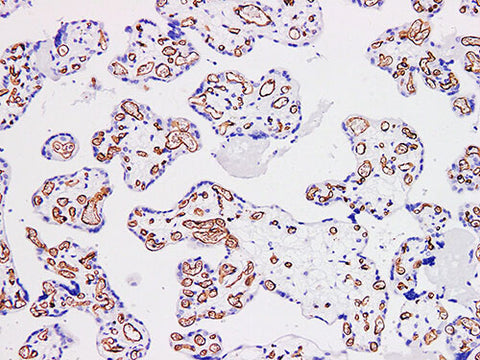

CD34 Monoclonal Antibody Stored at -20°C

Applications IHC-P

Tissue Specificity Placenta

CD34 is a single strand membrane penetrating protein with a molecular weight of 105~120 kDa, which is expressed in early LYMPHOPOIETIC stem cells, Progenitor cells, vascular endothelial cells, embryonic fibroblasts and some nerve tissue cells. It is mainly used for the differentiation of benign and malignant angiogenic tumors. CD34 and CD117 are used in the identity gastrointestinal stromal tumors. CD34 is positive in 80%~ 102% of dermatofibrosarcoma protuberans, which could be differentiated from dermatofibroma.